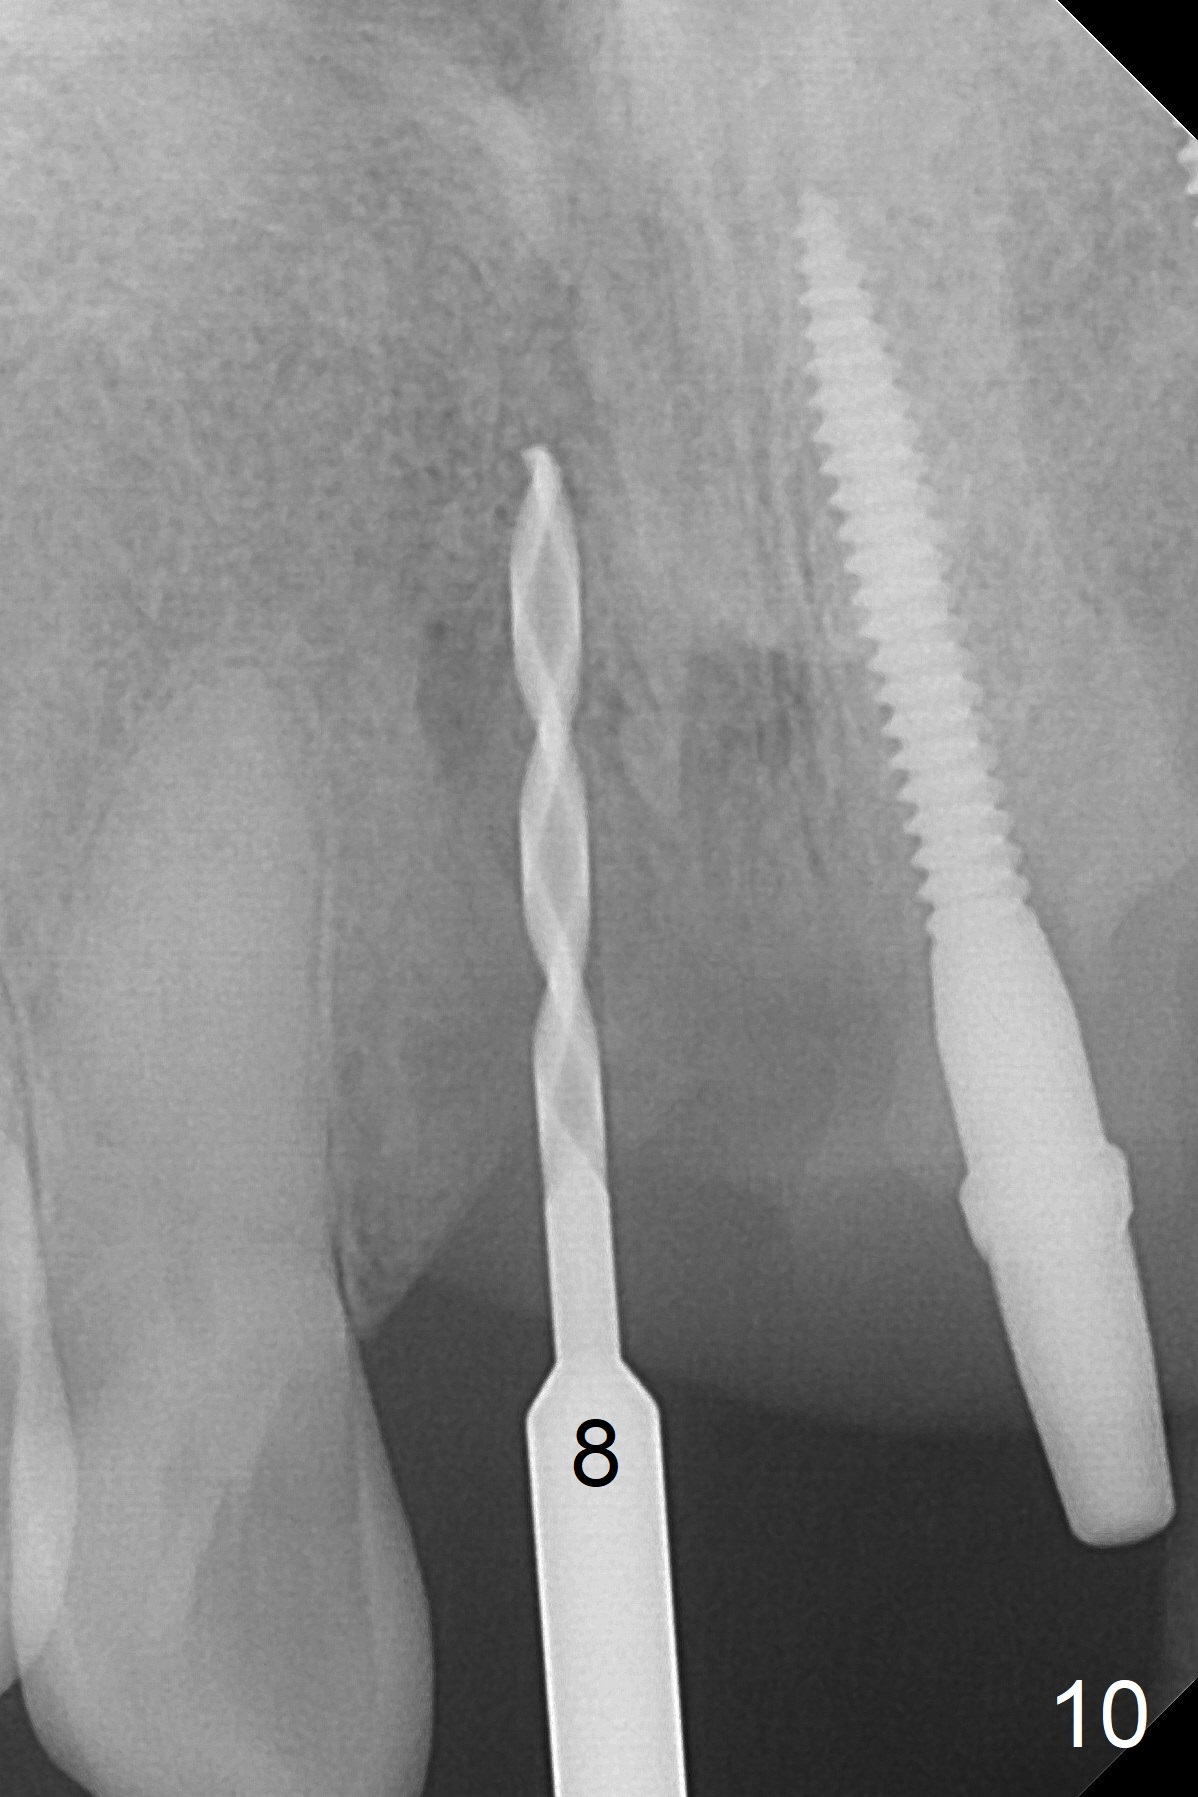

Change in trajectory at #8 seems acceptable (Fig.3 (arrowheads: upper midline suture)). But it relapses when a 2x14(2) mm implant is placed (Fig.4 (2x14(4) mm at #9)). It appears that a drastic change in trajectory is necessary (Fig.5). In fact it is difficult to change the trajectory with the flexible 1.2 mm drill. Lindamann bur can be used for this purpose initially (coronally). The osteotomy should be moved mesially prior to reuse of the 1.2 mm drill for depth (Fig.10) and re-placement of the 2x14(2) mm implant (Fig.11).